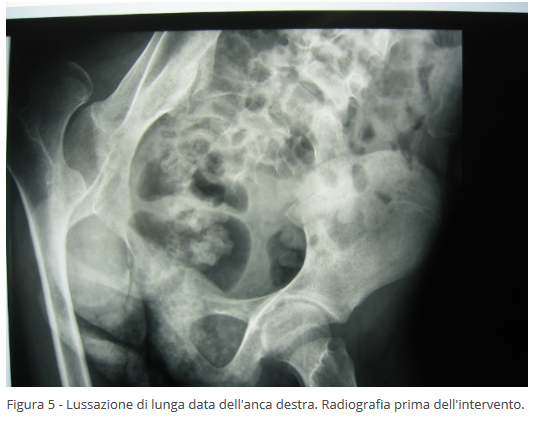

Il terzo livello di trattamento chirurgico delle deformità dell'anca nei bambini con paralisi cerebrale infantile avviene sul femore nei pazienti più grandi in cui non è più possibile ricondurre la testa del femore all'interno dell'acetabolo. Tale intervento prevede la resezione e l'asportazione della testa del femore in modo da non avere più attrito tra testa del femore  e bacino. Questo intervento si esegue in genere sopra i 15 anni di età, permette la risoluzione completa del dolore e il recupero dei movimenti della coscia (Figure 5-6).